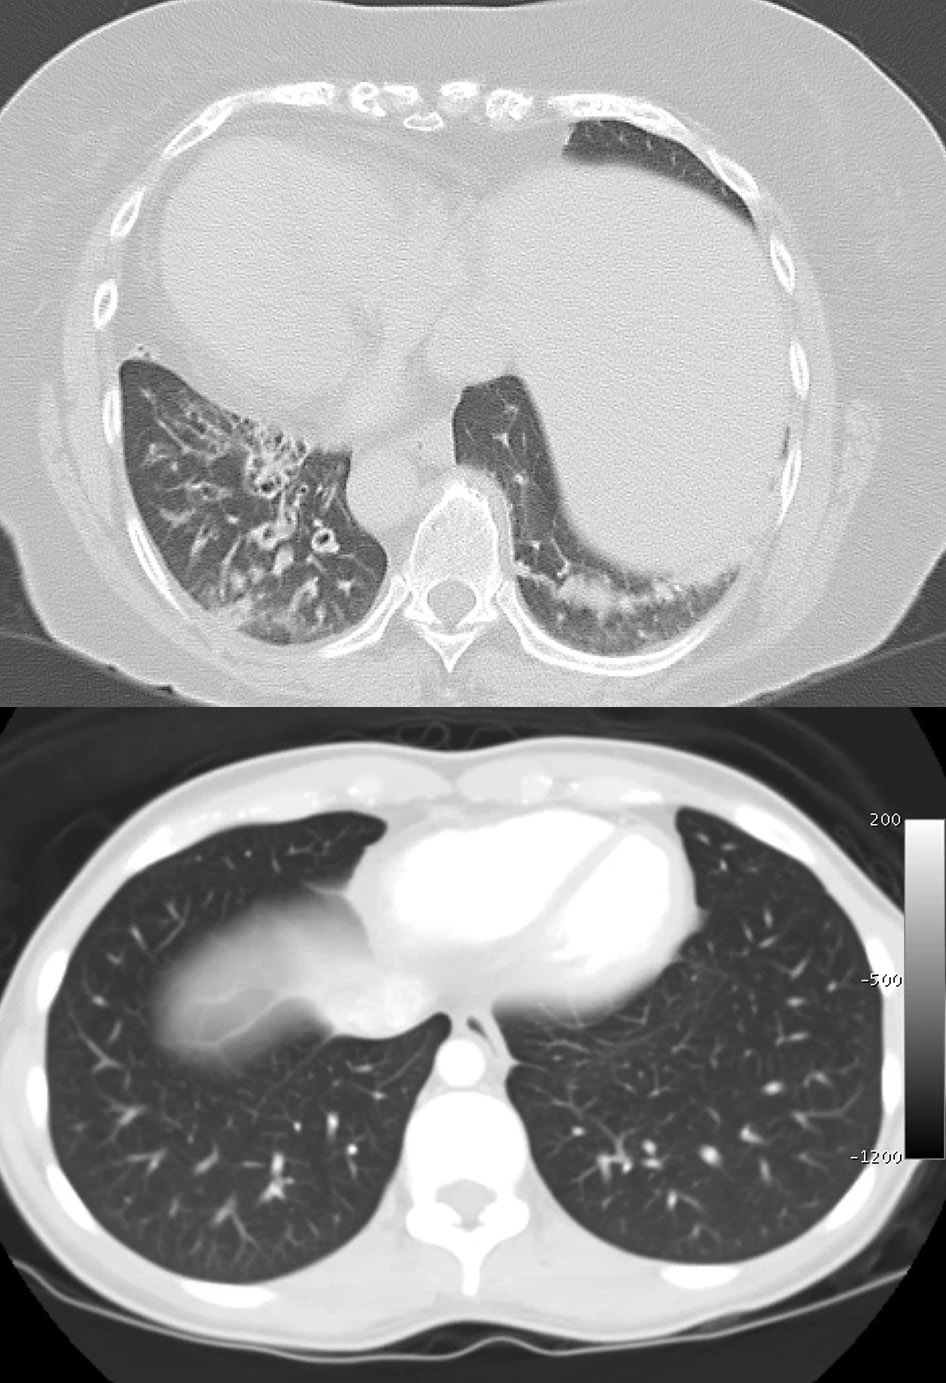

◂Chest CT for Internal Medicine Residents